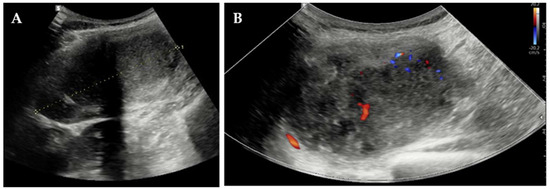

Elective excision was scheduled for August 2024 at our Clinic. Pre-operative blood tests, including complete blood count, hepatic and renal panels, and tumor markers, were within normal ranges, except for a mildly elevated α-fetoprotein level (8.5 ng/mL; reference < 5.8 ng/mL) while the patient was breastfeeding. Pre-operative US depicted an encapsulated, heterogeneous, moderately vascular mass measuring 86 mm (Figure 3) and suggested either endometriosis or splenosis.

Figure 3.

Pre-operative transabdominal US: (A) measurement of the lesion and (B) color-Doppler vascularization.